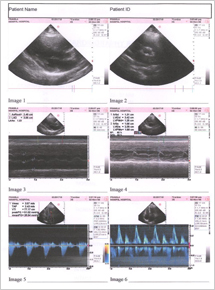

Echocardiography was done indicating a normal heart and patient is un symptomatic. Final Echocardiography was done and shown in FIG 4

FIG 4:- Echocardiography report of 4th JAN 2008